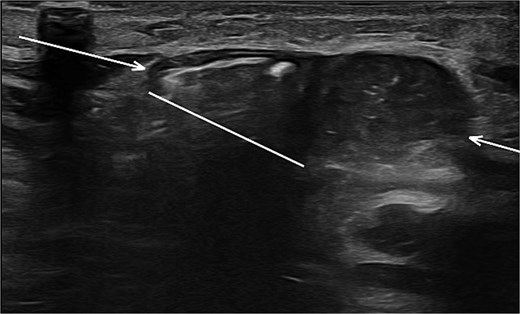

Sonographic imaging of the abdomen revealing a hernia defect (white line) and the hernial sac (white arrows).